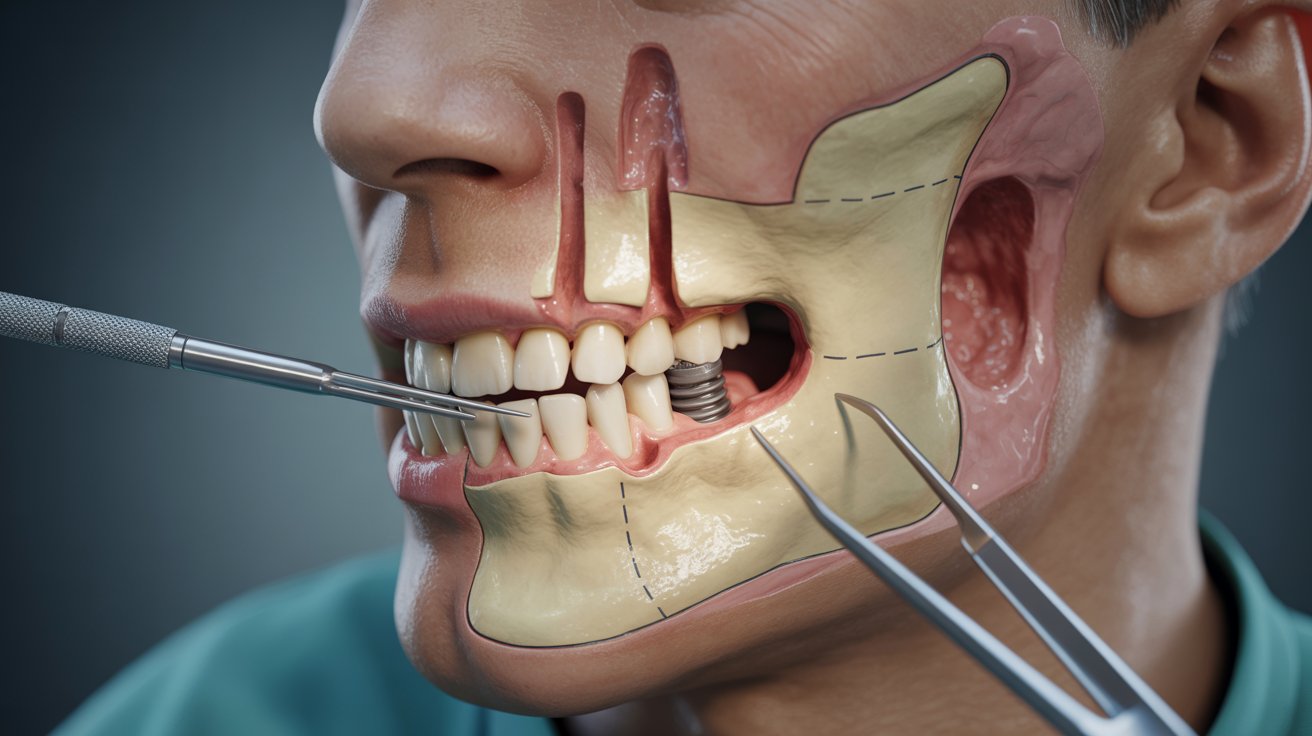

Traditional implants are placed into the jawbone and are ideal when you have adequate bone volume and density. When the upper jaw has resorbed (shrunk) substantially, conventional implants may first require sinus lifts or bone grafting, adding cost and time. Zygomatic implants are longer implants that engage the zygomatic bone (cheekbone)—a denser anchor—so clinicians can restore the upper arch even when the maxillary bone is too thin or soft for standard implants without major augmentation.

Zygomatic placement requires advanced imaging (CBCT), careful mapping of sinus and zygomatic anatomy, and a surgeon experienced with long, angled trajectories to the cheekbone. This specialized skillset and longer operating time contribute to higher fees.